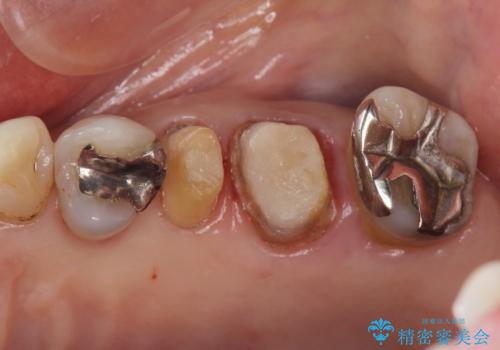

- 転倒して前歯を強打してかけてしまった、ぐらつくとのことで来院。

応急でみてもらった歯科医院で隣の歯と接着剤で留めてもらったとのこと。

歯の神経の状態を見たところ、前歯3本とも神経が死んでしまっていました。

また、左上犬歯の詰め物は途中で脱離し、セラミックでの修復をご希望されたため、一緒に治療しました。

根の治療を行い、ぐらつきに関しては様子を見て連結をするとのお話をさせていただきました。

結果ナイトガードの使用によりぐらつきはだいぶ回復してきたため連結はしていません。